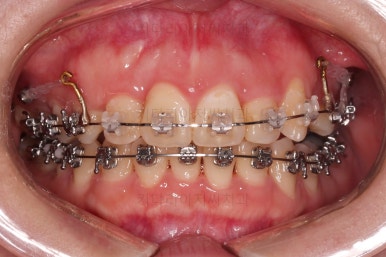

장치 부착 직후의 모습인데요.

아랫니는 발치 없이 가지런하게 해주고요.

윗니는 가지런하게 한 뒤 발치공간을 서서히 닫아줍니다.

유치는 크기가 작았기 때문에 생각보다 빨리 공간이 닫히고 있고요.

반대쪽 작은 어금니 부분은 공간이 아직 많이 남은 편이죠.

적절하게 틈도 다 모아주고요.

디테일을 정리하고 마무리를 하게 됩니다.

치료 종료 시 입안의 모습입니다.

윗니만 발치를 했지만 교합이 잘 맞고요.

한 쪽 송곳니가 없지만 기능적으로 전혀 문제를 못느끼실 교합을 맞춰놨고요.

위아랫니 가지런해졌고요.

대신 중앙선은 약간 틀어져 있는데요.

한 쪽은 송곳니가 없고 한 쪽은 작은 어금니를 발치했기 때문인데요.

18개월이라는 짧은 기간동안 부정교합, 덧니, 심지어 매복치아까지 개선했는데 양측 치아 사이즈 문제로 생기는 중앙선 정도는 아무 문제가 안되는거죠.